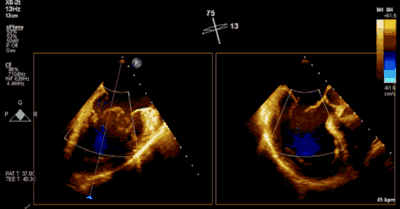

患者全麻以后,在经食道超声心动图和X射线引导下,经股静脉入路,将MitraClip瓣膜夹顺利送至二尖瓣前后叶交界中心处,成功捕捉二尖瓣前叶A2和后叶P2,经超声心动图反复确认瓣叶夹持牢固后,测定有效夹持长度10.4mm,评估反流量降至轻度,释放瓣膜夹,超声心动图评估瓣膜夹位置和功能良好,测定左房压降至26/12mmHg,再次评估反流量仍为轻度,手术顺利完成。

▲ 术后超声检查显示轻度二尖瓣反流

王焱、王斌教授团队通过术前和台北荣民总医院(Taipei Veterans General Hospital)宋思贤教授进行了详细的讨论并制定了最优的手术策略,同时术中视频连线获得宋思贤教授的技术支持,华体会体育官方网站 超声内科苏茂龙教授负责术中超声心动图引导。患者全麻以后,在经食道超声心动图和X射线引导下,经股静脉入路,将MitraClip瓣膜夹顺利送至二尖瓣前后叶交界中心处,成功捕捉二尖瓣前叶A2和后叶P2,经超声心动图反复确认瓣叶夹持牢固后,测定有效夹持长度11mm,评估反流量降至微量,释放瓣膜夹,超声心动图评估瓣膜夹位置和功能良好,测定左房压降至11/6mmHg,再次评估反流量仍为微量,手术顺利完成。